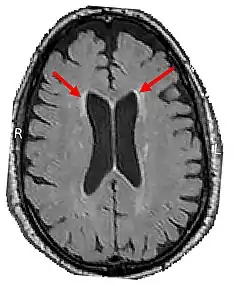

LENAS is seen with damage to the white matter and axons within the brain. The external human LENAS brain shows findings in several major structures. There is mild atrophy of the frontoparietal regions of the brain and a mild reduction of the thalamus and rostral (front) part of the caudate nucleus (which is located in an area of the brain called the basal ganglia).[4] Abnormalities in the frontal, frontoparietal, and temporal lobes are most severe and predominant with LENAS and asymmetry of the cerebral hemispheres has sometimes been found.[4] LENAS also may show moderately enlarged lateral ventricles and atrophy in corticospinal tracts as well as in the pons.[4]

- Longitudinal MRI studies annually can potentially also help with prognosis. This was found from another study which found that, as throughout the disease course, the more rapid the confluence of patchy or focal T2-weighted hyperintensities and the progression of cortical atrophy suggests the poorer the prognosis appears to be.[12][13][11]